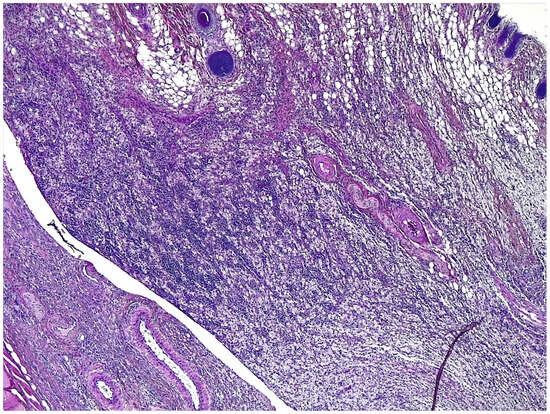

2.3. Histological Evaluation and Immunohistochemical Analysis

| Cells layers at margins of the granulomas | 3 (2–3) | 2,5 (2–3) | 0.59 |

| Inflammatory reaction in the host tissue | 3 (2–4) | 2 (2–3) | 0.23 |

| Inflammatory response on the mesh surface | 3 (2–4) | 3 (2–4) | 0.63 |

| Tissue maturation | 3 (2–4) | 2 (1–3) | 0.28 |

| COX % cell | 2 (1–3) | 2 (1–3) | 0.59 |

| COX intensity | 2 (1–3) | 2 (1–3) | 0.52 |